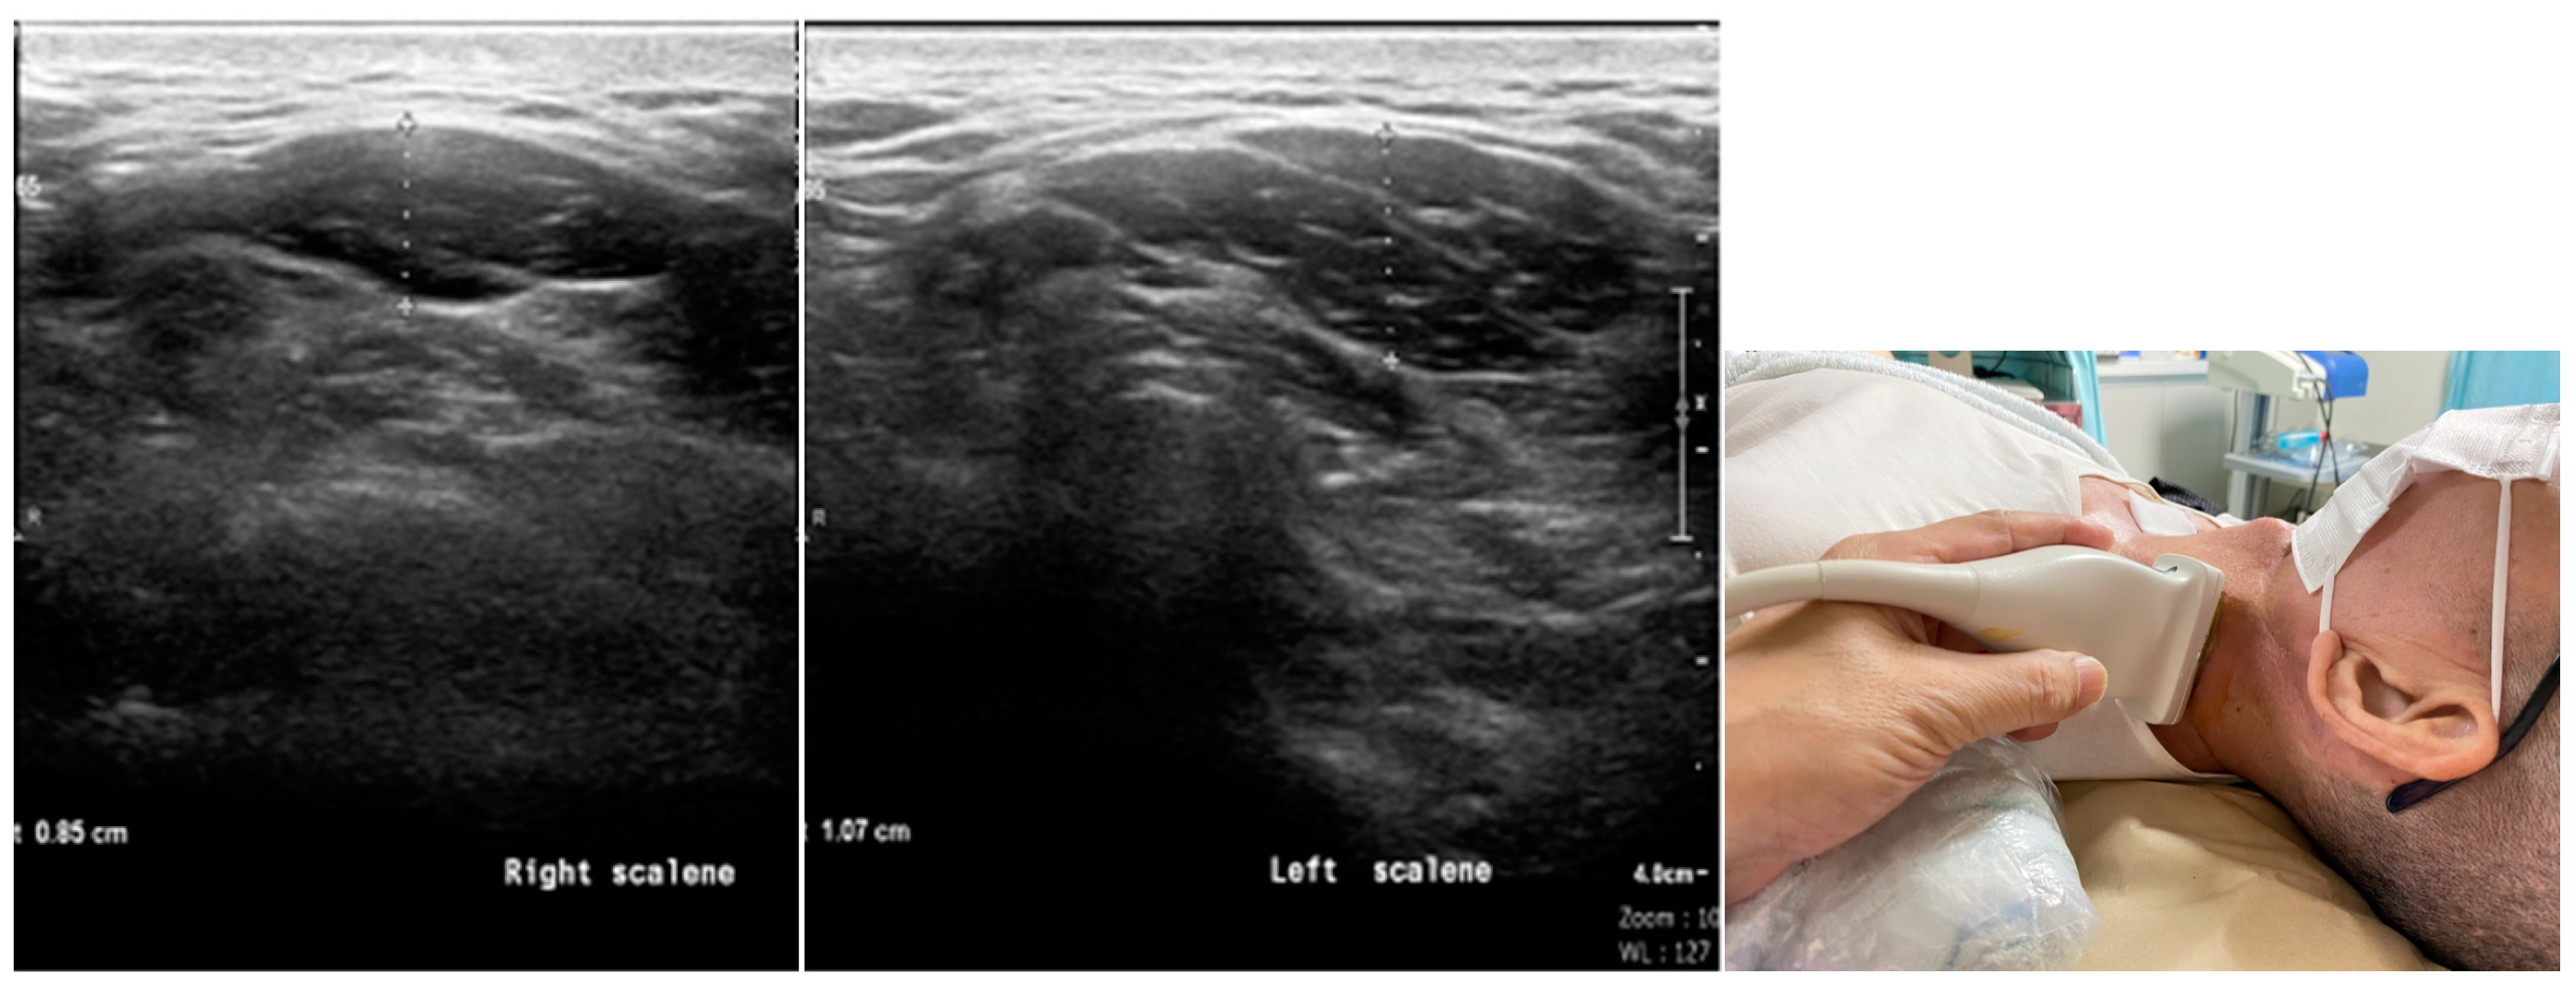

2.2. Ultrasound Examination